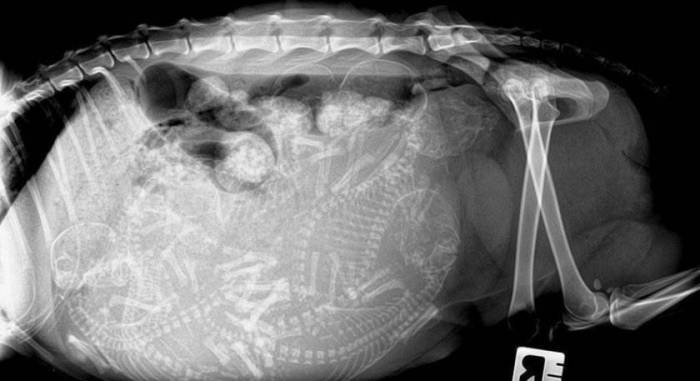

Рентген — метод это не самый полезный для самой кошки и будущих котят, поэтому прибегать к нему нежелательно. Увидеть четкие контуры плодов на рентгеновском снимке можно с 45-го дня беременности.

Ультразвуковое исследование — с его помощью можно не только увидеть будущее потомство, подсчитать количество малышей, но и услышать сердцебиение. Метод чаще всего применяется, если есть необходимость определить беременность кошки на ранних сроках.

- На 25-й день можно сделать анализ крови на наличие релаксина (гормона, специфичного для беременности у собак и кошек), а также на 25-28 день с помощью пальпации определить наличие плодов в матке. Рентгеновское исследование покажет беременность не ранее 40-го дня.

Если раньше ветеринар мог лишь нащупать плоды в животе, то с 40-го дня он сможет точно сказать количество ожидаемых котят.